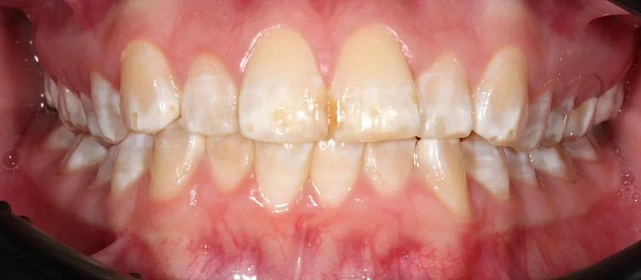

Нарушение соотношения челюстей и неправильное положение зубов — зубные ряды смыкались некорректно, зубы стояли со смещением.

Проблема: Пациентку не устраивало положение зубов и то, как смыкаются челюсти. Зубы стояли неровно, ряды сходились неправильно.

Прозрачные элайнеры Click на обе челюсти. Выровнять зубы и нормализовать смыкание. Основной набор — 20 кап. Срок — около 1 года.